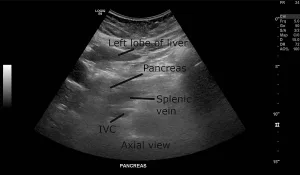

Pictures of the outside are useful, but images from the inside—like ultrasounds—tell an even richer story. When my own doctor sent me for imaging, I was terrified…and wildly curious. What would it show? Turns out, ovarian cancer images ultrasound aren’t pretty, but they’re powerful confessionals. They spot pockets of fluid, odd-shaped masses, and changes in texture that doctors are trained to see—but that a thousand Google searches just can’t match.

What Will an Ultrasound Show?

- Fluid buildup (aka ascites) that looks different from normal tissue

- Solid lumps or tumors—not just harmless, water-filled cysts

- Changes in the lining of the abdomen or ovaries

Want to see some typical scans? There’s a great selection of ovarian cancer images ultrasound that show what doctors look for. Sometimes the cancer is big and obvious. Sometimes, it’s tiny—and only a careful eye or a trained professional can tell something’s wrong. That’s why you shouldn’t self-diagnose from photos. Let your doc (or a friendly radiologist) do the detective work. But if you’re a visual learner like me, it definitely helps to know what might actually show up on those screens!